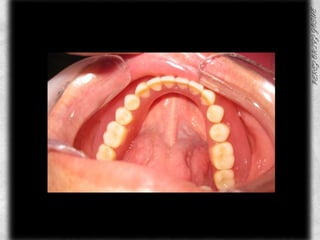

ARCADA SUPERIOR CLASIFICACIÓN DE OSAWA TIPO IFORMA DE PROCESO “U”LINEA MEDIA COINCIDE CON EL RAFE PALATINOCOLOR ROJO BRILLANTETEXTURA LISAPROCESO ALVEOLAR TIPO IAPARENTEMENTE SIN PRESENCIA DE CANDIDABUENA INSERCION DE LOS FRENILLOS